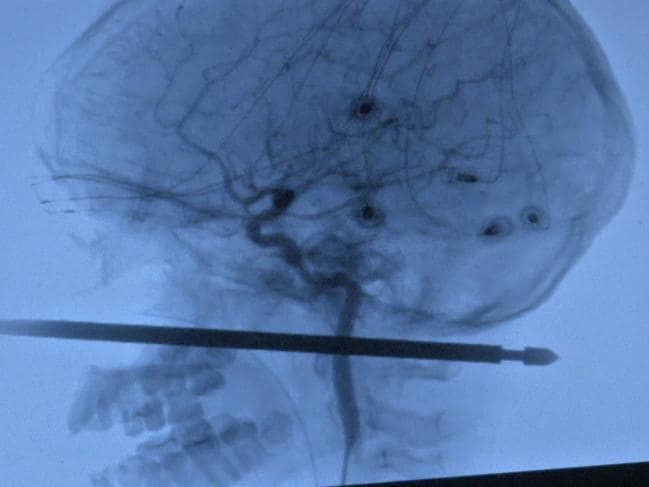

Όπως εξήγησε, η ράβδος διαπέρασε τον λαιμό και το κεφάλι του αγοριού χωρίς όμως να πλήξει τα μάτια, τον εγκέφαλο τον νοτιαίο μυελό και τα μεγάλα αγγεία.

Κατά την πτώση του, καρφώθηκε ακριβώς πάνω στην τετράγωνη μεταλλική ράβδο και μεταφέρθηκε στο Παν/κο Νοσοκομείο του Κάνσας, όπο νοσηλεύεται μέχρι σήμερα.

Το παιδί οδηγήθηκε σε 3 διαφορετικά νοσοκομεία για να αφαιρεθεί η ράβδος και να αντιμετωπιστούν τα τραύματά του.

Η εγχείρηση ολοκληρώθηκε επιτυχώς την Κυριακή και δεν υπάρχει αιμορραγία, ωστόσο αναμένεται να πάρει εξιτήριο τουλάχιστον στις αρχές της επόμενης εβδομάδας.